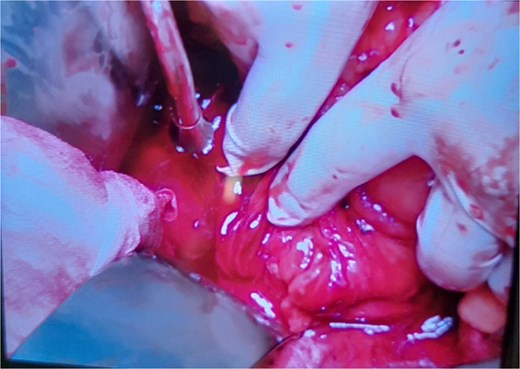

Intraoperative findings included rupture of the superior mesenteric vein at two sites, resulting in massive hemoperitoneum; >95% circumferential disruption of the second and third portions of the duodenum with only minimal posterior serosal continuity; laceration of the pancreatic uncinate process; jejunal perforation; ischemic perforation of the transverse colon due to mesocolon devascularization; and a right retroperitoneal hematoma (Fig. 2). The pancreas was markedly swollen, precluding reliable assessment of parenchymal or ductal injury at that time. Given the hemodynamic instability, damage control surgery was performed, which included repair of the superior mesenteric vein, segmental resection of the transverse colon with proximal colostomy, small bowel repair, and temporary closure of both ends of the disrupted duodenum. A nasogastric tube was inserted for bile drainage. The operation lasted ~3 hours, with an estimated blood loss of 5000 ml.